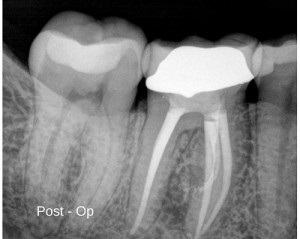

This patient’s symptoms resolved within days and she has been asymptomatic since. My expectation is that we will see a significant reduction in the size of the lesion at our one year recall. Most dental office may treat 10-15 lower molars in an average year. One could expect then to find one mid-mesial canal every couple of years. While enhanced optics and 3D imaging surely helps with the discovery process, the dentist must be vigilant to be on the lookout for these black sheep canals.